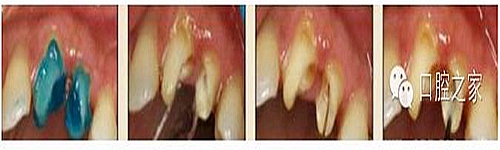

大多數(shù)醫(yī)生在樁道預(yù)備時習慣于干燥預(yù)備根管(圖 1),這樣很容易破壞根管壁的牙本質(zhì)結(jié)構(gòu),同時也可形成較厚的玷污層,影響樹脂水門汀與牙體組織的粘接。因此,臨床操作時應(yīng)選擇沖洗的方法冷卻預(yù)備根管(圖 2),防止牙膠及封閉劑粘連附著于根管壁形成第二玷污層(根管治療時形成的玷污層稱為第一玷污層),有利于樹脂水門汀與根管牙本質(zhì)的粘接。

圖1:干燥預(yù)備根管。

圖2:沖洗預(yù)備根管。